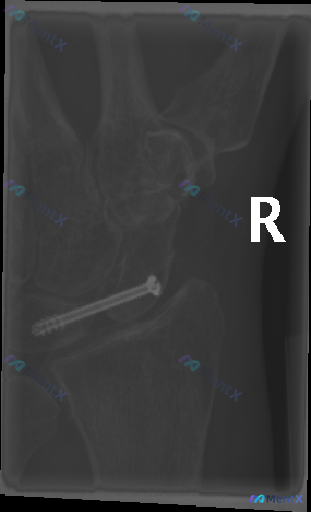

整理到一份右手腕部的影像资料,和大家讨论一下。 基本情况:右腕舟骨骨折术后复查 影像表现: - 投照为右手腕部斜位X线片,显影涵盖桡骨远端、尺骨远端及部分腕骨 - 舟骨位置可见一枚金属内固定螺钉(无头加压螺钉),穿过舟骨长轴,螺钉在位,未见明显断裂 - 可见一清晰的透亮线横贯舟骨腰部,位于螺钉路径附...